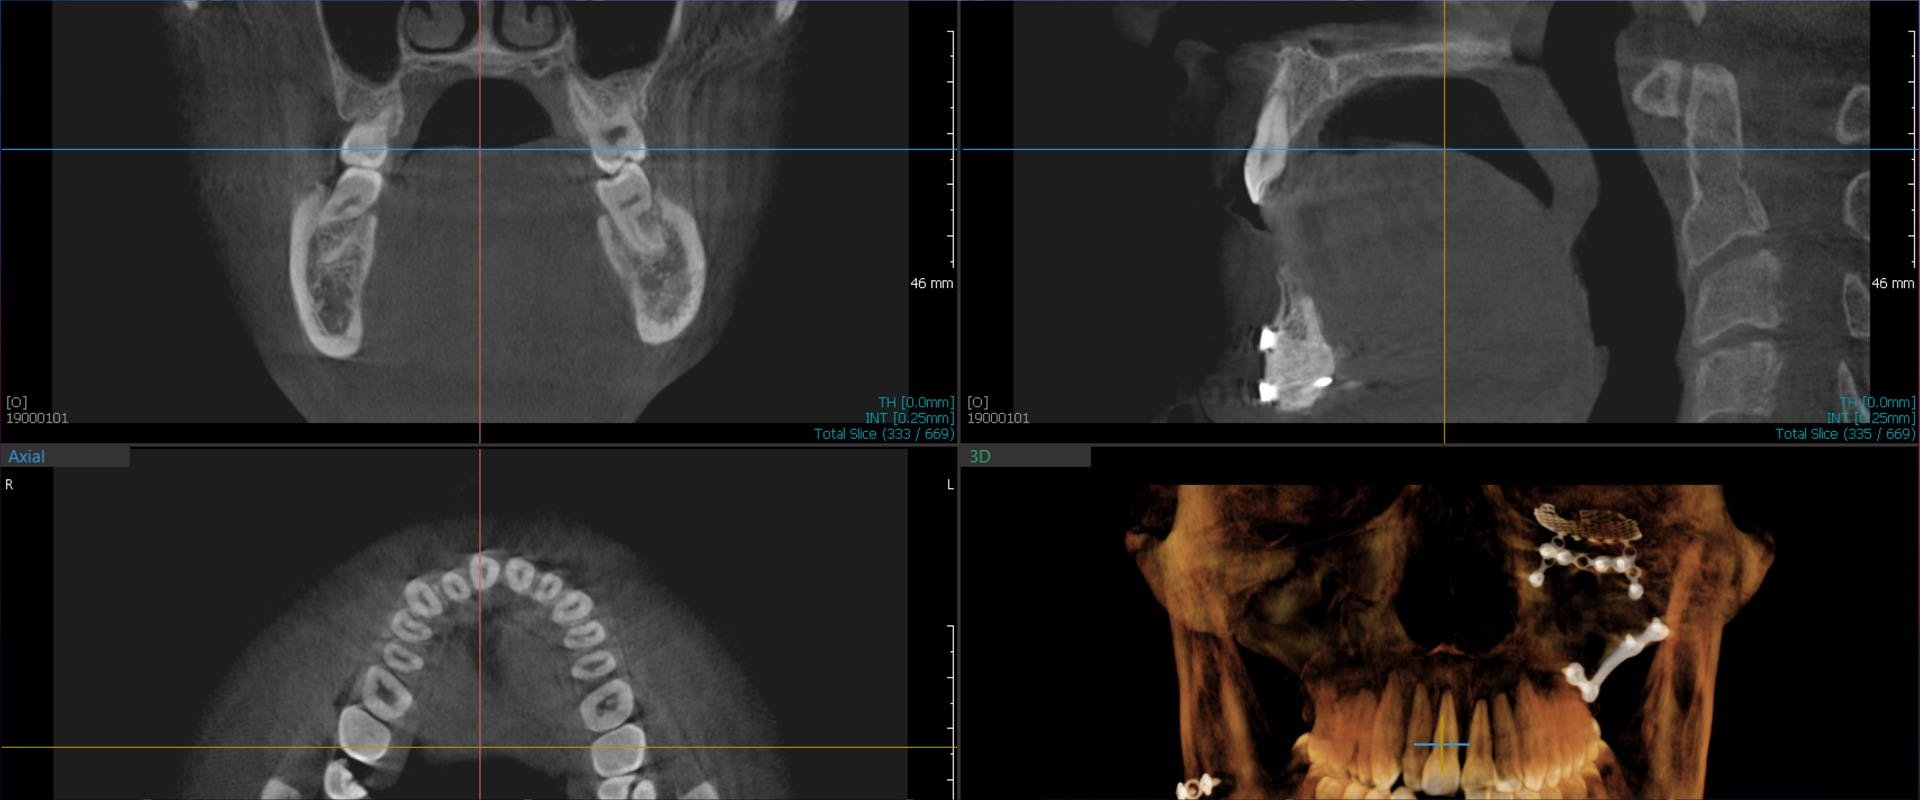

Das DVT und seine vielfältigen Indikationen

In dieser Fortbildung erhältst du Einblicke in die digitale Volumentomographie (DVT), die sowohl in spezialisierten Feldern wie der zahnärztlichen Chirurgie und Implantologie als auch in allgemeinzahnärztlichen Praxen zunehmend an Bedeutung gewinnt. Du wirst über die spezifischen Indikationen, bei denen die DVT zweidimensionalen Bildern überlegen ist, informiert und lernst die Fälle kennen, in denen traditionelle Ansätze vorteilhafter sein können. Zudem deckt die Fortbildung gesetzliche Anforderungen ab, insbesondere den Strahlenschutz und die rechtfertigende Indikation gemäß Strahlenschutzverordnung. Anhand praxisnaher Beispiele aus verschiedenen zahnmedizinischen Disziplinen wie Chirurgie, Implantologie, Prothetik, Parodontologie, Endodontie und Kieferorthopädie wird dir gezeigt, wie diese Technologie die Diagnostik und Patientenversorgung in deiner Praxis verbessern kann.